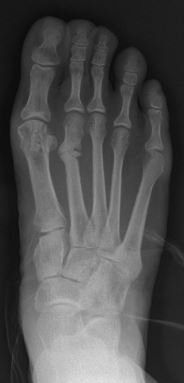

Для усталостного перелома характерны весьма малые осколки кости и микротрещины[4]. Чаще всего данный вид перелома возникает в несущих костях, такой как берцовая кость, плюсневые и ладьевидные кости, иными словами в костях голени и стопы. Менее распространен усталостный перелом бедра, таза и крестца[5].

Рентгеноскопическое исследование обычно не выявляет усталостный перелом сразу, однако по истечении нескольких недель после возникновения боли на рентгенограмме можно заметить перестройку кости. Наиболее эффективными инструментами диагностики на раннем этапе являются сканирование при помощи компьютерной томографии, магнито-резонансной томографии[7].